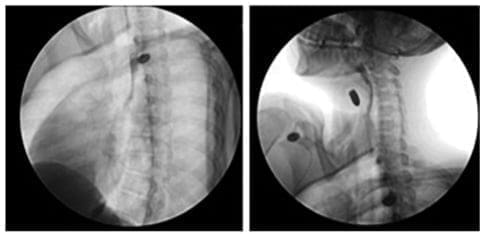

Ante la sospecha clínica de lesión vascular cervical como primera posibilidad, se tomó una radiografía de tórax postero-lateral que descartó la presencia de neumotórax, hemotórax u otra complicación (figura 3).

Figura 3. Radiografía anteroposterior de tórax observando una adecuada expansión pulmonar, sin encontrar hemotórax o neumotórax y sin derrame pleural. Fuente: los autores.

Figura 6. Esofagograma con contraste oral hidrosoluble, observando un trayecto y calibre normal, sin extravasación del medio de contraste o presencia de trayectos fistulosos. Fuente: los autores.

Se realizó un esofagograma que no mostró fugas o lesiones fistulosas (figura 6), y una nasofibrolaringoscopia que documentó un hematoma hemilaríngeo derecho (figura 7); este examen se repitió a las 24 horas sin observar cambios respecto al estudio inicial.